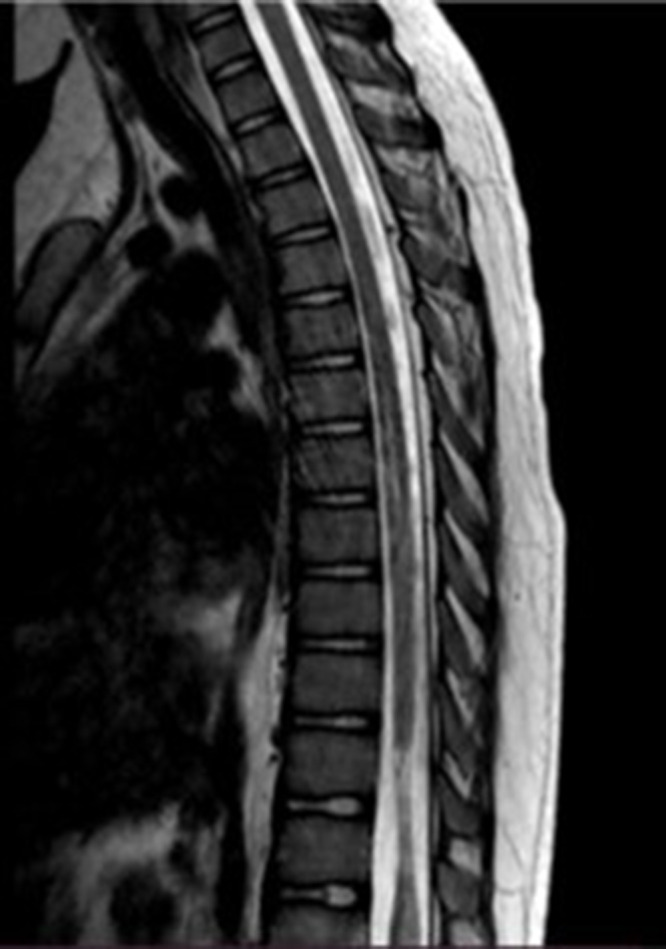

Case presentation: The case of acute transverse myelitis in a 12-year-old child corresponds to the existing definition of a vaccine-associated paralytic poliomyelitis case: a temporal relationship between the onset of flaccid paralysis and the administration of oral polio vaccine and the duration of paralysis. The child developed flaccid paralysis 18 days after (August, 2024) the administration of oral polio vaccine and persisted for more than 60 days from the onset of the disease. Vaccine virus type 3 was isolated from the feces. However, the child received 2 doses of inactivated oral polio vaccine and 1 dose of bivalent (types 1 and 3) oral polio vaccine before the disease. The child did not have an increase in the titer of antibodies in paired sera to polioviruses types 1 and 3. Spinal cord magnetic resonance imaging revealed an intramedullary focus with hyperintense MR signal on 2WI, 2FS at the level of the spinal cord cone (Th11-L2), which spread across the entire diameter and unevenly accumulated paramagnetic. These changes were characteristic of acute transverse myelitis.